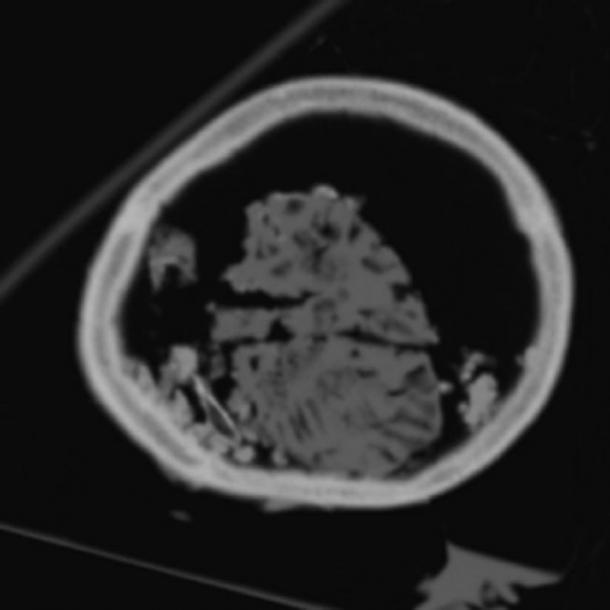

Sección de tomografía computarizada del cráneo que muestra dos de los fragmentos más grandes, que pueden ser los hemisferios cerebrales separados por la hendidura sagital. ( David King )

Después de un examen más detallado del cráneo, se observó que contenía una masa elástica que no era consistente con la arcilla y el limo marrón oscuro. Cuando los investigadores inspeccionaron el asunto a través de la cavidad endocraneal a través del agujero magno, se reveló que había una presencia de material amarillo que finalmente se reveló que era el cerebro.

La materia cerebral se había encogido en el cráneo pero aún era reconocible. Aunque la morfología de la superficie del órgano se conservó y se mezcló con capas de sedimento mixto, su conservación se atribuyó a varios factores con los que se enterró la cabeza cortada.